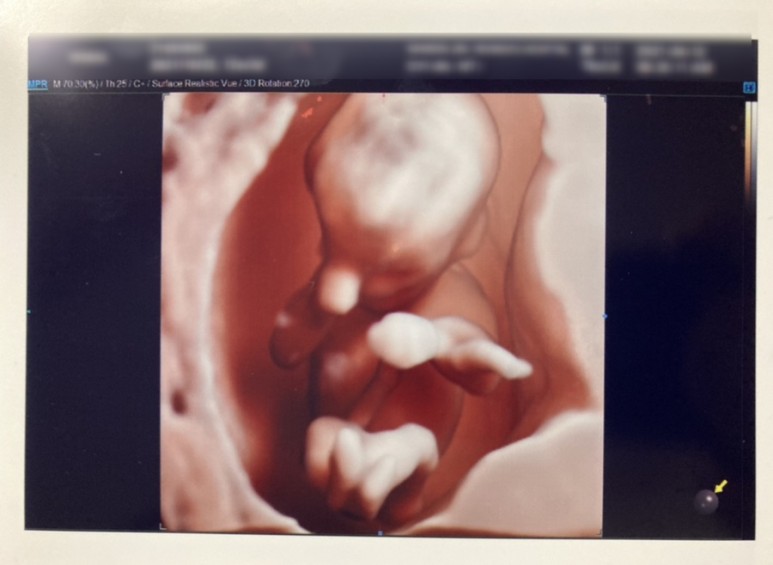

이제 제법 사람 같네.8주 동안 매주 병원에 다녀왔다.그냥 한방이 건강한지 보고 싶어서 ㅎㅎ 또.. 병원 검진휴가 하루 쉬면서 남편이랑 데이트도 좋아하고..

왼쪽사진은 한방을 밑에서 찍은모습이고 궁에들어와 양다리www11주차가 된 한방은 이미 꽤 사람같았다. 그리고 이날 초음파를 봤는데, 아무리 움직여도, 아기 집을 팡팡 발로 차고, 손도 엉망진창이여서, 너무 귀여웠다. 벌써부터 도치맘…?